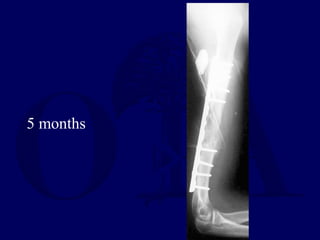

5 months

5 months Free fibulagraft fixation with long T plate